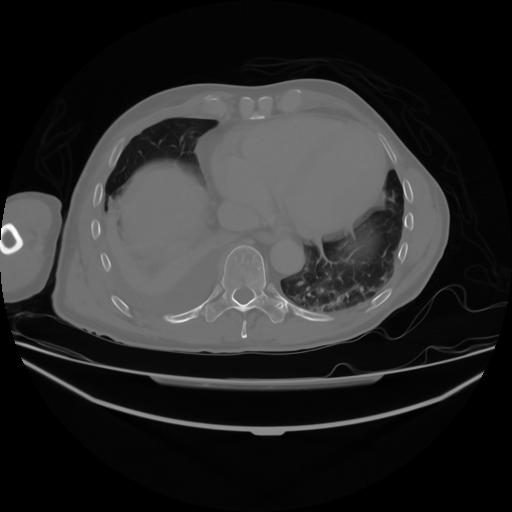

4 CUERPO,CE,Axial,3.0,CUERPO,,